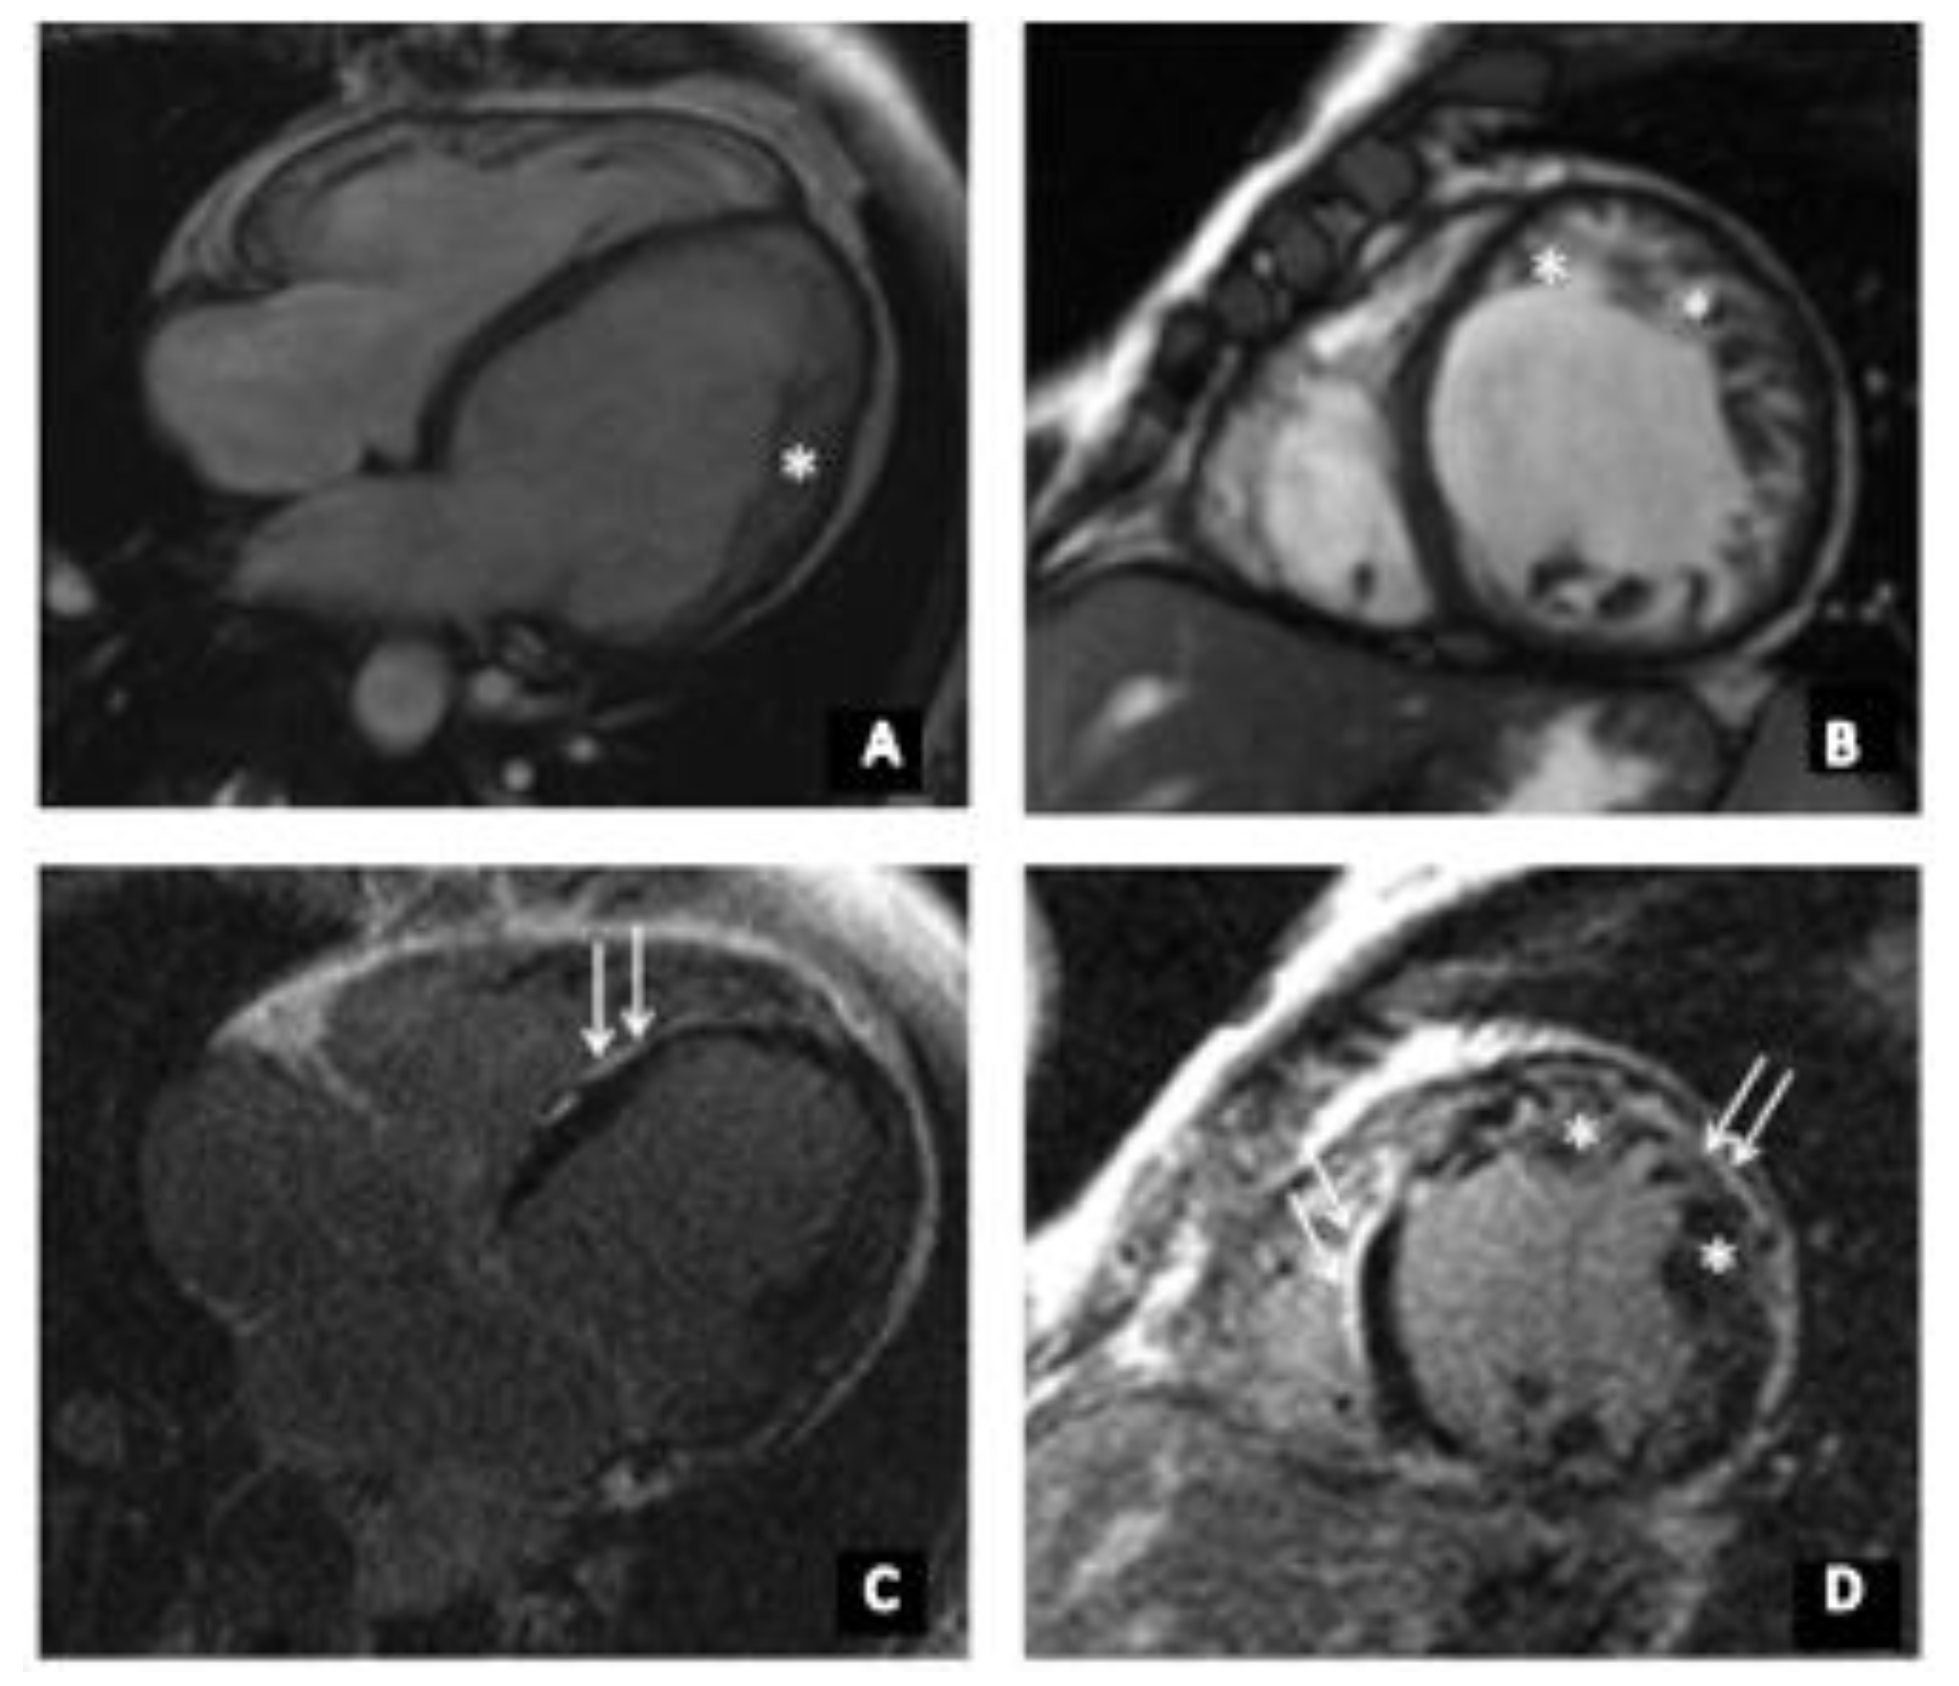

Figure 2.

(A–D) cardiac MRI of index patient (II-2). * indicates non-compact myocardium (up to 18 mm). (A) Long-axis four-chamber projection, steady state free prcession (SSFP), and (B) short axis, SSFP, (C,D) Late gadolinium enhancement, areas of non-ischemic (subepicardial) contrast enhancement of left-ventricular walls are indicated with the white arrows.

At the age of 35, she had acute respiratory viral infection (ARVI), lasting for about a month with febrile temperature and severe asthenic syndrome. Afterwards, she began to note the worsening of heart failure, shortness of breath when climbing to the second floor, and a decrease in exercise tolerance. ECG detected a left bundle branch block (LBBB). Echocardiography revealed an ejection fraction (EF) of 42% and the left-ventricular end diastolic diameter (LVED) was 6.3 cm. In addition, left-ventricular (LV) diffuse hypokinesis was found. HM-ECG showed a sinus rhythm with heart rate of 34–151, frequent premature supraventricular beats (PSVB), and premature ventricular beats (PVB). She received β-blocker therapy and an angiotensin-converting enzyme inhibitor, which the patient independently canceled due to poor health. At the age of 36, she was admitted to the National Medical Research Center for Therapy and Preventive Medicine (Moscow, Russia). Her expressed muscle weakness while climbing the stairs attracted our clinical attention. According to echocardiography, the signs of a non-compact LV myocardium were detected in the apex, lateral, anterior, and posterior walls with the formation of non-compacted cardiomyopathy. It is impossible to exclude transferred myocarditis, with a decrease in LV systolic function up to 28%. To clarify the diagnosis, the patient underwent cardiac MRI with gadolinium (Figure 2), which showed a two-layer structure of the LV myocardium in the lower, anterior, anterolateral, and lower lateral segments, corresponding to the criteria for LVNC (in more than six segments). Thickness of the compact layer in these segments was 1.8–3.4 mm, and non-compacted was 10–17 mm. The non-compacted layer was presented by a spongy myocardium. The indexed mass of a non-compacted myocardium was 41 g/m2 (at a rate of up to 15 g/m2), which was 37.7% of the mass of the LV myocardium (at a rate of up to 25%), and ejection fraction (EF) was 31%. Tests for cardiotropic viruses were negative. According to the HM-ECG, non-sustained ventricular tachycardia (NSVT) was detected, and the patient received amiodarone for treatment of arrhythmia. Electroneuromyography revealed a muscle lesion level with mild signs of the ongoing breakdown of muscle fibers in the thigh muscle. At the age of 37, a cardiac resynchronization therapy device (CRT‑d) was implanted due to the presence of heart failure, reduced EF, and the presence of LBBB (QRS > 160 m/s). The patient’s condition remained stable, in view of which she independently reduced her therapy. Thus, instead of a decrease in EF to 23%, an increase in pulmonary systolic pressure (PSP) was noted during a planned examination in 2020. Currently, the patient constantly receives bisoprolol 2.5 mg, perindopril 2.5 mg, torasemide 5 mg, spironolactone 25 mg, and warfarin 5 mg. The father of the index patient (Figure 1A, I-1) died at the age of 52. Although no detailed clinical data are available, a cardiomyopathy can be suggested. At the age of 16, the first son of the index patient (Figure 1A, III-1) developed muscle weakness and an unexpressed shortness of breath with significant exertion. At the age of 18, an ambulatory examination was carried out with respect to the identified disease of the mother. Echocardiography showed signs of non-compacted myocardium (Chin criteria). The heart chambers were not expanded. Diffuse hypokinesis was found. HM-ECG showed episodes of sinoatrial (SA) blockade of the second degree. Cardiac MRI with gadolinium suggested LVNC (Figure 2). There were no signs of myocarditis.